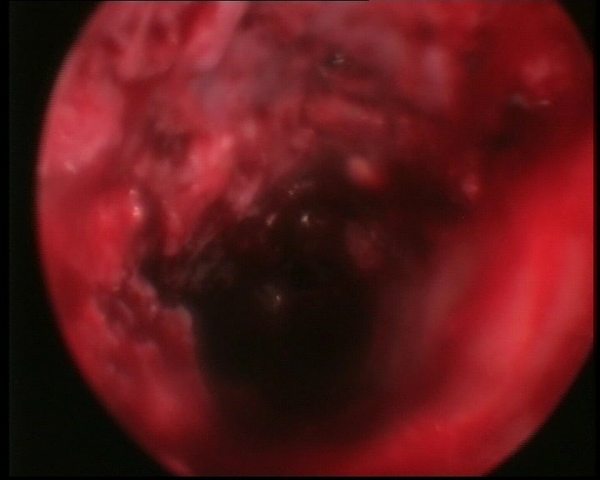

Определенным подспорьем в решении вопроса о жизнеспособности кости (а это определить часто очень сложно) может служить эндоскопия костно-мозгового канала (медуллоскопия), которую мы пробуем выполнять в подобных ситуациях. При высоких переломах голени это сделать не сложно (рис. 1, данная фотография взята из зарубежной статьи). Можно использовать лапароскоп (мы так и делали), урологический цистоскоп, артроскоп. После удаления штифта перед рассверливанием канала эндоскопия малоинформативна, так как поверхность кости закрыта патологическкими грануляциями и соединительнотканными разрастаниями в виде бахромы (рис. 2, виден конец канюлированного винта, через который мы вводили жидкость в костно-мозговой канал). Однако после рассверливания канала можно хорошо видеть участки кости, которые имеют серый цвет и не кровоточат, или же наоборот, имеют вид жизнеспособных (рис. 3). Манипуляцию целесообразно делать под жгутом на бедре. Наилучшая визуализацию обеспечивает постоянное промывание жидкости через костно-мозговой канал.